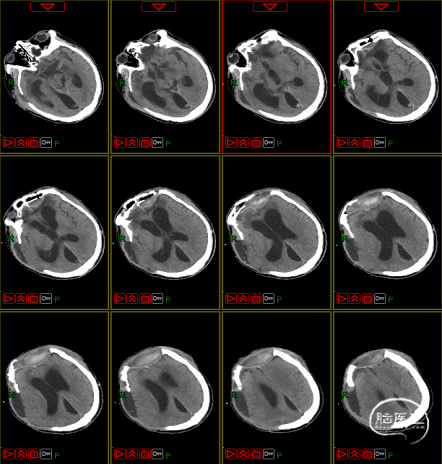

4. 动态复查头部CT

8月21日复查CT:硬膜下积液增加,脑室扩张明显,间质性水肿加重;对患者治疗方案进行调整,转神经外科治疗。

脑积水的处置